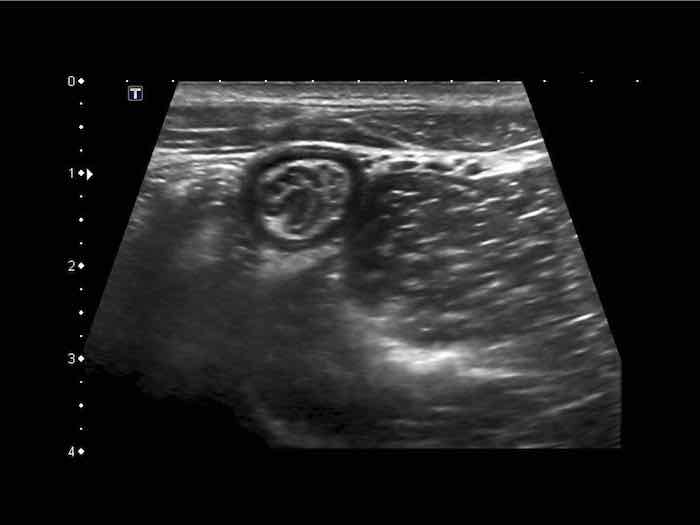

Đây là hình ảnh siêu âm của một trẻ 2 tuổi bị lồng ruột hồi manh tràng từng đợt, được khám trong khoảng thời gian giữa các cơn.

Hồi tràng với nhiều mảng Peyer sa vào manh tràng.

Hình ảnh siêu âm kinh điển của lồng ruột hồi-manh tràng ở hai trẻ khác nhau.

Trong cả hai trường hợp, đoạn hồi tràng bị lồng được định vị không đối xứng bên trong ống lồng ngoài, do mạc treo ruột tăng âm có chứa mỡ, bám vào hồi tràng và đi theo hồi tràng khi bị kéo vào trong.

Trong mạc treo, siêu âm cho thấy một hạch bạch huyết mạc treo (hbh) phóng đại ở cả hai.

Các hạch này phì đại như một phần của tình trạng tăng sản hạch bạch huyết toàn thân và khônghu trú trong lòng hồi tràng.

Do đó đây không phải là điểm dẫn đầu nguyên phát. Ở bệnh nhân bên phải, ruột thừa (mũi tên) cũng bị kéo vào trong.

Lưu ý cấu trúc đa lớp của thành bụng phía trước của phức hợp lồng ruột, đại diện cho ba lớp thành ruột bị gấp lại.